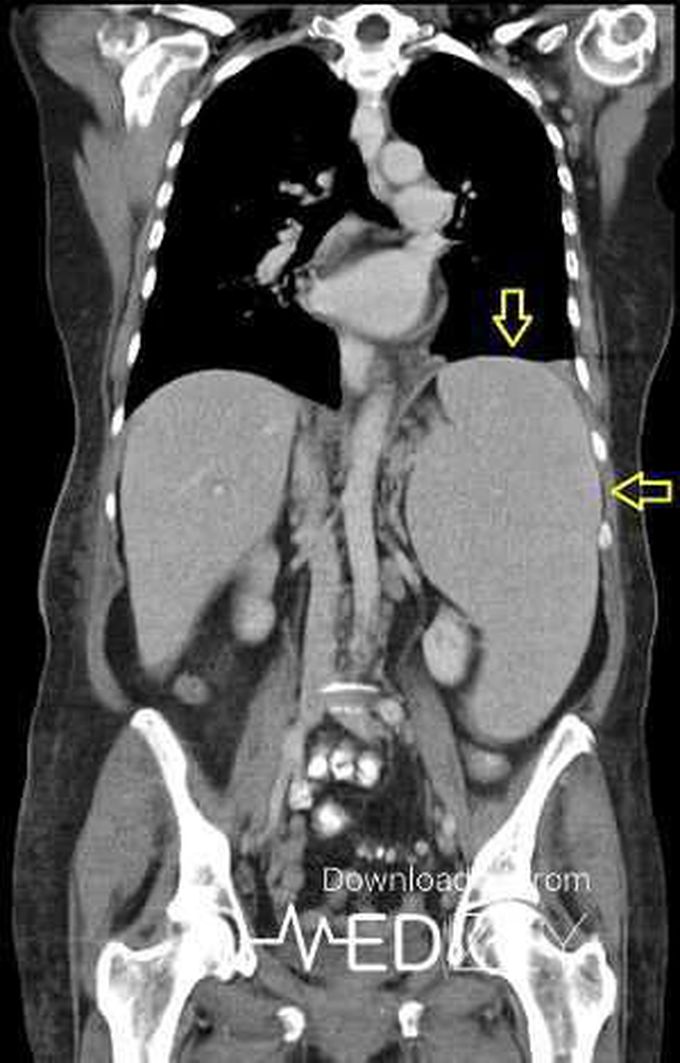

Splenomegaly

Spleen

Palpable

10rib